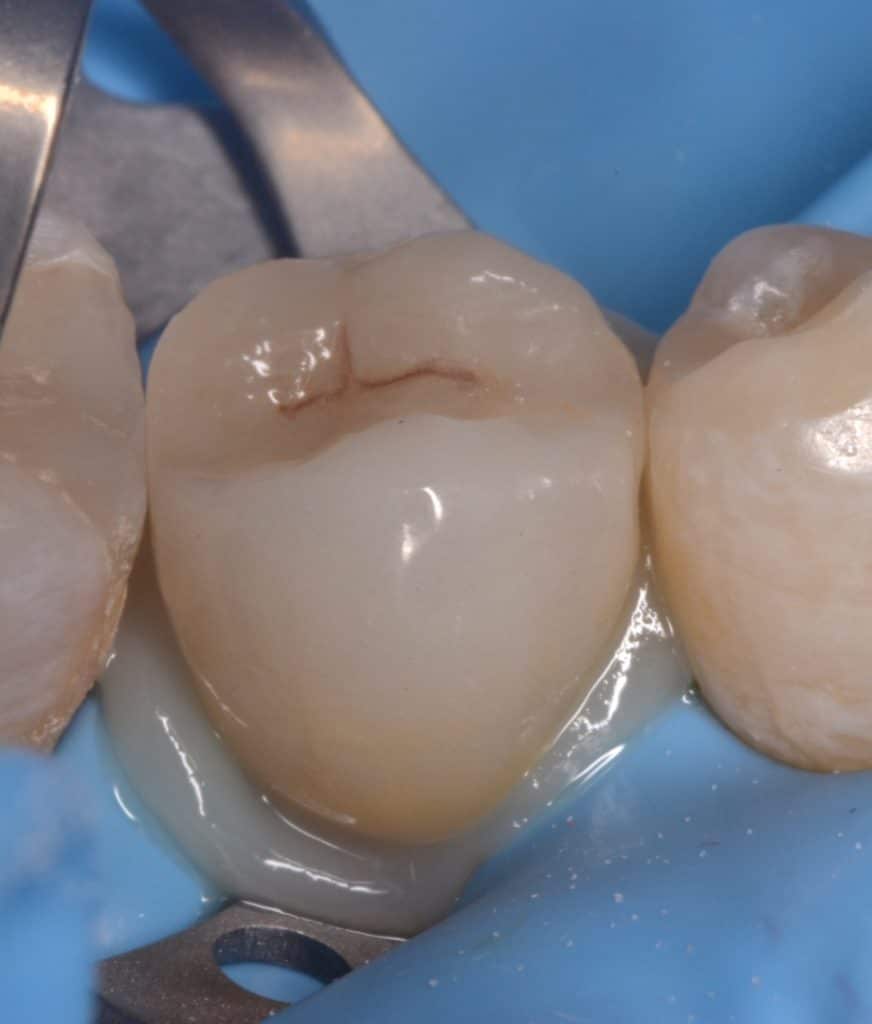

Initial situation showing badly carious lower second premolar

Buccal view showing the same destruction of the tooth, the patient insisted on restoring her tooth

Isolation, look to the amount of tooth structure left under the gingival tissue, dentin quality looks good for bonding, so lets go with adhesive dentistry